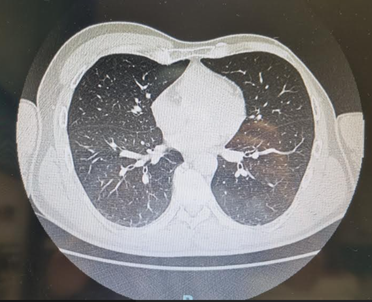

We report the case of a 19-year-old Man, born at term, with no evidence of consanguinity or medication taken during gestation. Presents with left thoracic depression affecting his quality of life without functional impairment. Physical examination revealed depression of the left chest wall responsible for asymmetry of the two hemithoraxes (Figures 1,2). The neurological and skeletal examination was normal. A thoracic CT scan was performed, revealing agenesis of the sternocostal insertion portion of the left pectoralis major with total agenesis of the pectoralis minor and hypoplasia of the anterior arches of the first six homolateral ribs (Figure 3) corresponding to Poland syndrome. A malformation assessment using abdominal ultrasound and X-rays of both hands was carried out, revealing no associated malformation, particularly renal and upper limb bones.

Figure 3: Axial computed tomographic images of the thorax showing: hypoplasia of the left pectoralis major muscle with absence of the heads with sternocostal insertion.